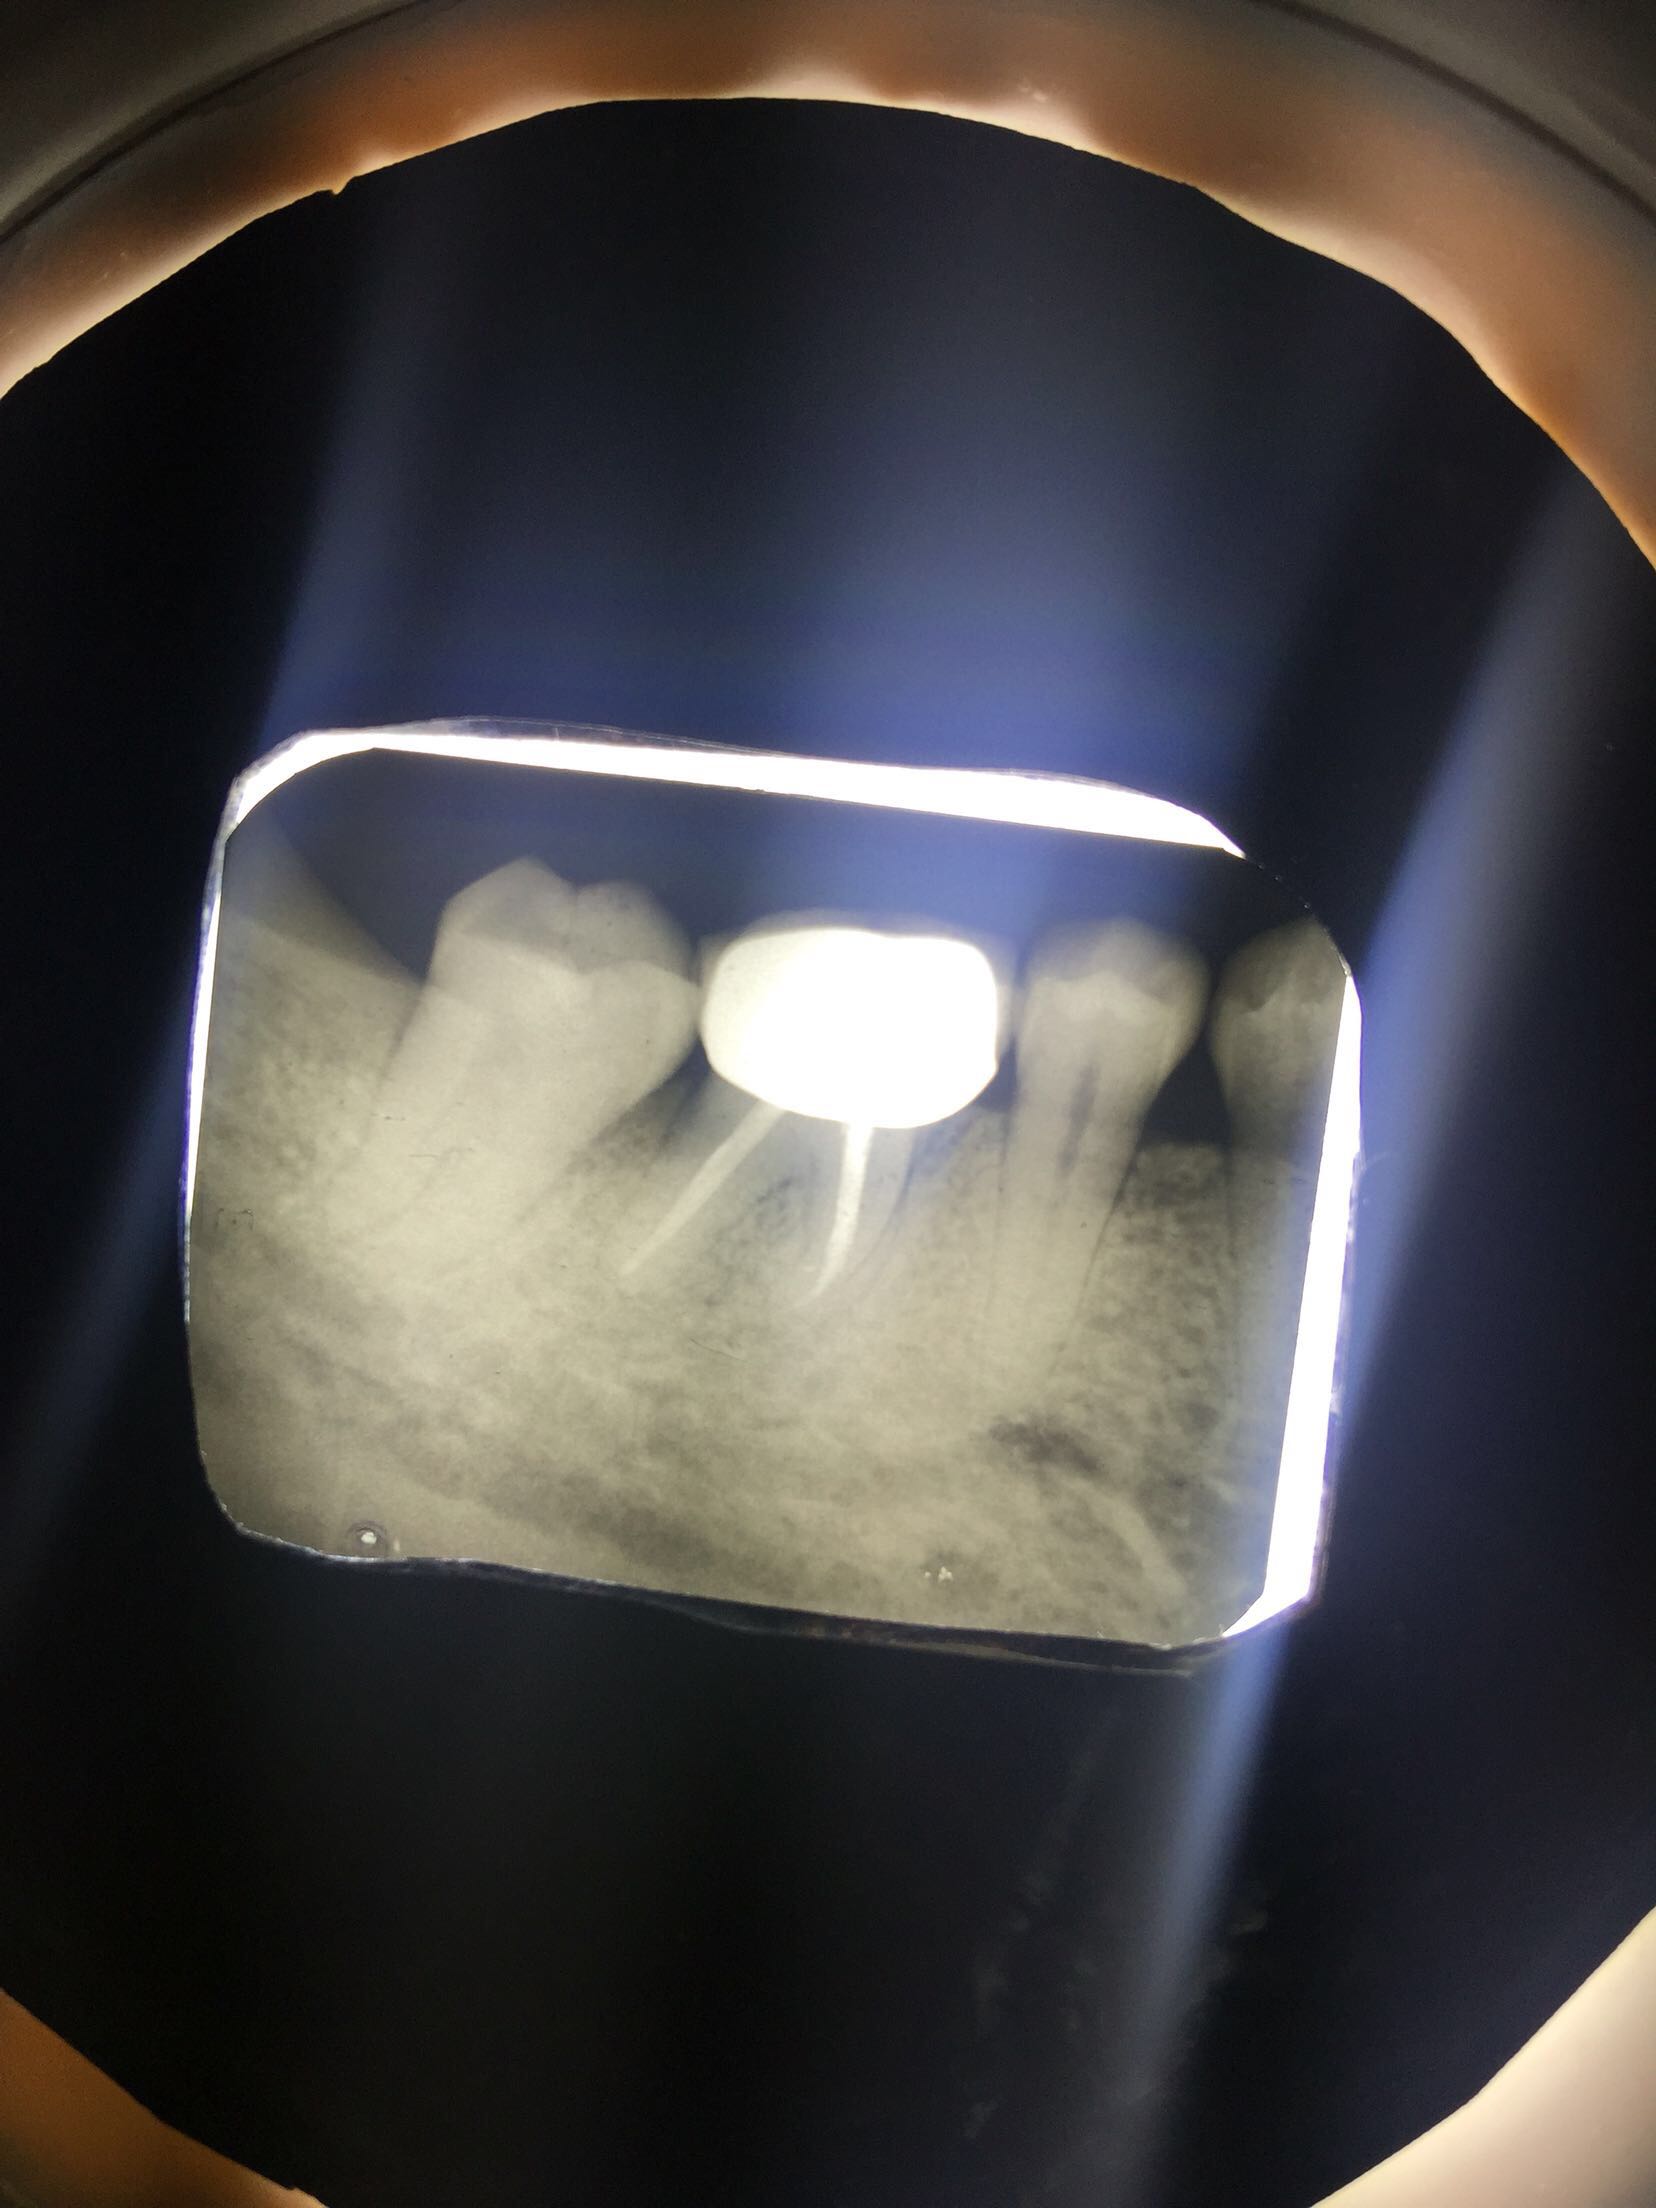

检查:36冠修复,叩诊(+-),松动II度,颊侧牙龈瘘管,牙周袋约3mm,根分叉未探及,冷(-)。 X线示:36根尖区及根分叉区大面积阴影。

诊断:36牙周牙髓联合病变 治疗:告知患者36预后差,治疗效果不理想,如炎症控制不好拔牙可能,患者要求试着保留患牙。 36拟行完善RCT及牙周刮治术,观察根尖区及根分叉愈合情况。 36常规根管治疗后行牙周刮治术,术后牙龈瘘管消失。

20个月复查,36牙龈无红肿,牙体无松动。X线示36根尖及根分叉病变愈合。